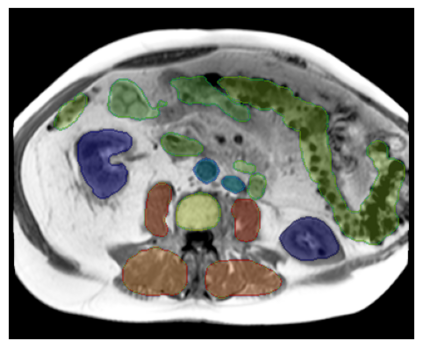

Purpose: To introduce a deep learning model capable of multi-organ segmentation in MRI scans, offering a solution to the current limitations in MRI analysis due to challenges in resolution, standardized intensity values, and variability in sequences. Materials and Methods: he model was trained on 1,200 manually annotated MRI scans from the UK Biobank, 221 in-house MRI scans and 1228 CT scans, leveraging cross-modality transfer learning from CT segmentation models. A human-in-the-loop annotation workflow was employed to efficiently create high-quality segmentations. The model's performance was evaluated on NAKO and the AMOS22 dataset containing 600 and 60 MRI examinations. Dice Similarity Coefficient (DSC) and Hausdorff Distance (HD) was used to assess segmentation accuracy. The model will be open sourced. Results: The model showcased high accuracy in segmenting well-defined organs, achieving Dice Similarity Coefficient (DSC) scores of 0.97 for the right and left lungs, and 0.95 for the heart. It also demonstrated robustness in organs like the liver (DSC: 0.96) and kidneys (DSC: 0.95 left, 0.95 right), which present more variability. However, segmentation of smaller and complex structures such as the portal and splenic veins (DSC: 0.54) and adrenal glands (DSC: 0.65 left, 0.61 right) revealed the need for further model optimization. Conclusion: The proposed model is a robust, tool for accurate segmentation of 40 anatomical structures in MRI and CT images. By leveraging cross-modality learning and interactive annotation, the model achieves strong performance and generalizability across diverse datasets, making it a valuable resource for researchers and clinicians. It is open source and can be downloaded from https://github.com/hhaentze/MRSegmentator.